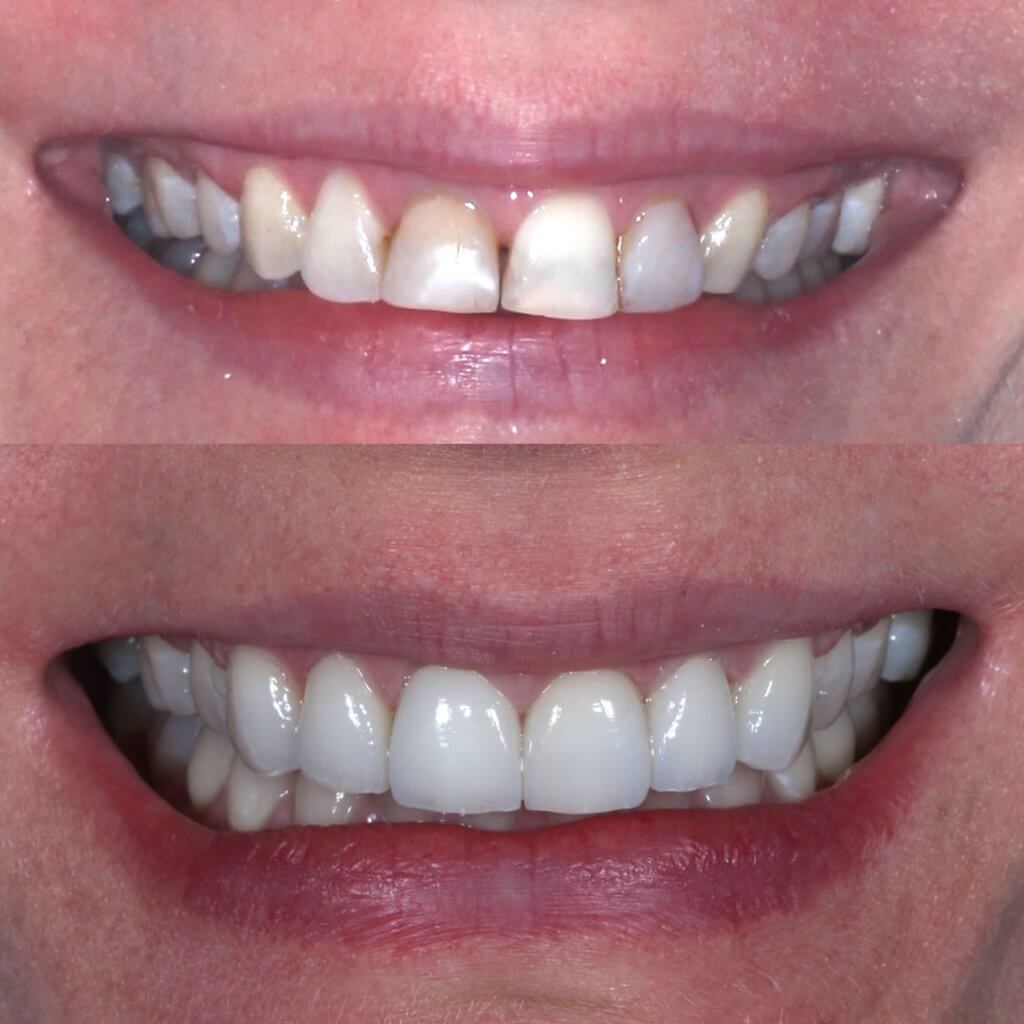

Facetas

Facetas e próteses são realizadas para melhorar a forma e cor dos dentes deixando mais estéticos. Também são realizadas quando os dentes perdem grande parte da sua estrutra, assim conseguem substituir a estrutura dental de forma estética e resistente.